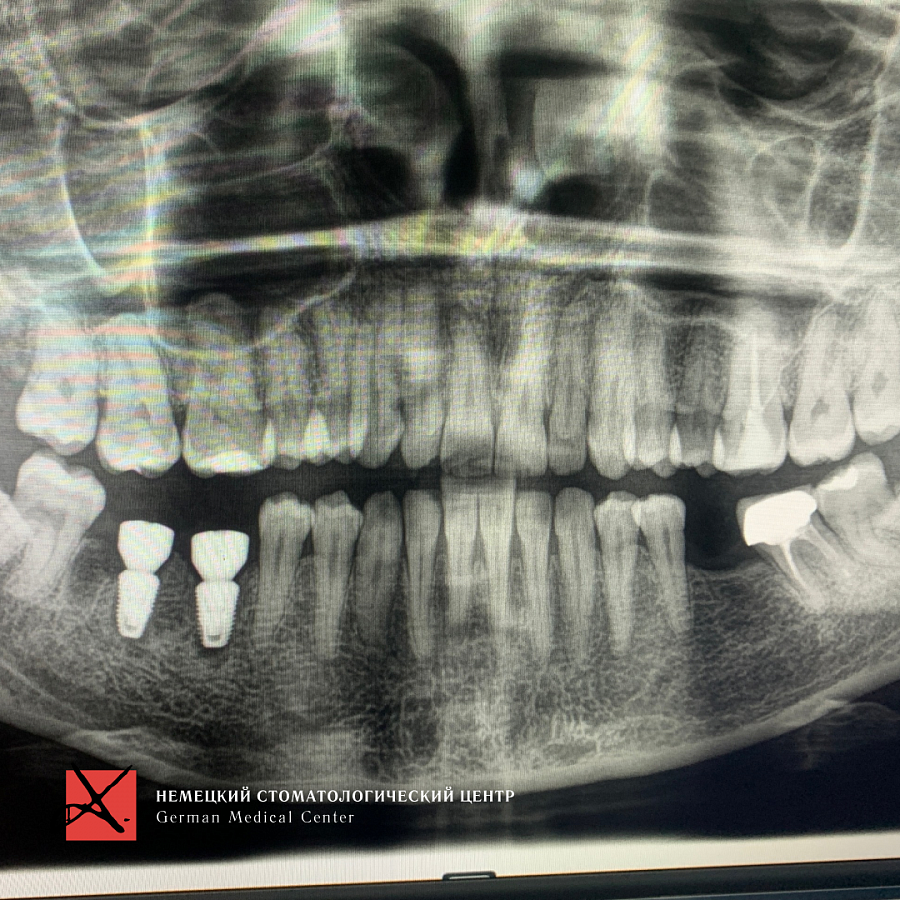

Пациентка обратилась с жалобой на перелом зуба, который ощутила при накусывании.

Провели имплантацию при помощи хирургического шаблона, который позволяет максимально точно спроектировать и спозиционировать положение имплантата для будущей функциональной нагрузки, грамотного распределения давления на имплантаты, а также здоровья зубного импланта. Операция прошла успешно.